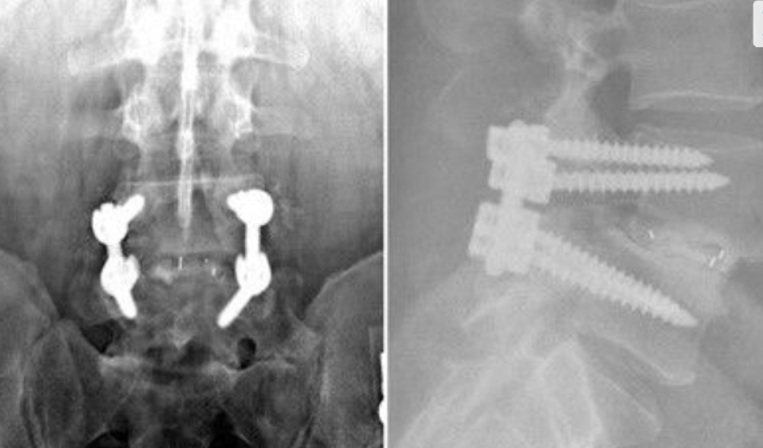

After Surgery Results

The surgeon removes the damaged disc or diseased bone, places a cage or bone graft between the vertebrae, and secures it with screws and rods. Over months, the bones heal together naturally. The surgical approach (front, back, or side) depends on the patient's specific condition and body type.